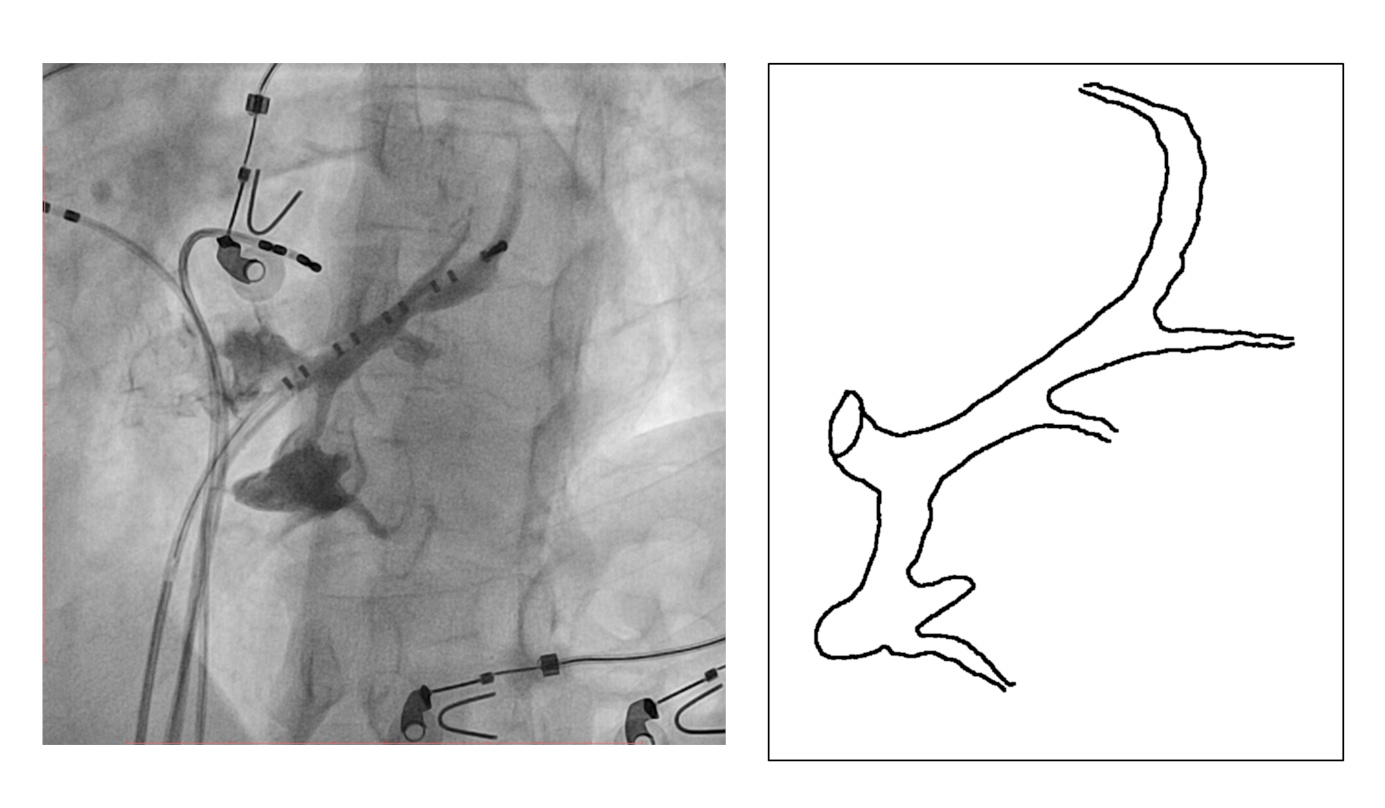

Mapping in diverticulum

diverticulum.jpg

med_lat_div.jpg

signals.jpg

Mapping in diverticulum - CSE potential most important

div_schematic.jpg

Selvaraj RJ et al. Radiofrequency ablation of posteroseptal accessory pathways associated with coronary sinus diverticula. J Interv Card Electrophysiol. 2016 Nov;47(2):253-259. doi: 10.1007/s10840-016-0113-x.